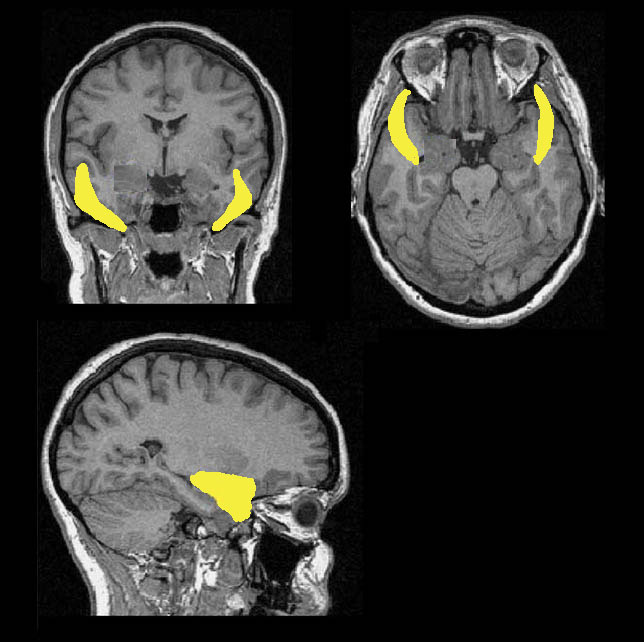

Я уже несколько лет вместе с коллегами в институте Дондерс в Голландии, а теперь и в Высшей школе экономики изучаю вопрос: что происходит у нас в голове, когда мы понимаем, что думаем не так, как другие? Оказалось, в этот момент становится активной эволюционно древняя область, которая реагирует на ошибки, — передняя цингулярная кора.

Цингулярная кора находится в средней части мозга и отвечает за адаптацию. Еще в этом процессе участвует так называемая Система 1, которая состоит из орбитофронтальной коры, амигдалы (ее еще называют миндалевидным телом) и прилежащего ядра. В ней вырабатывается медиатор дофамин, отвечающий за удовольствие. Цингулярная кора и Система 1 вместе делают так, чтобы в будущем мы не совершали ошибок и отказывались от мнений, которые расходятся с мнением большинства.

Мы с коллегами захотели посмотреть на работу этих систем в ситуации, когда мнение человека расходится с мнением большинства, и провели эксперимент. Студентка по фотографиям оценивала красоту 200 незнакомых женщин. ФМРТ-сканер фиксировал сигналы ее мозга и показывал активность в обычных условиях, когда нужно оценить красоту лица. После этого мы сообщали девушке, как на тот же вопрос ответили 100 других студенток ее университета, и фиксировали сигналы еще раз. У нас получалось две картины: когда девушка формировала собственное мнение и когда она знала, что ее мнение не совпадает с мнением большинства.

Когда участница считала кого-то непривлекательным, а потом выясняла, что большинство оценило того же человека как красивого, сигнал в цингулярной коре был очень мощным: «Ты не права, измени свое мнение!»

Позже ученые в Гарвардском университете провели похожий эксперимент, но добавили еще один этап: во второй раз показывали людям фотографии, которые вызвали расхождение мнений. Они хотели проверить, начинает ли нам нравиться то, что нравится другим. Оказалось, что да. И здесь уже действовала Система 1.

В рискованном поведении участвуют две зоны мозга. Первая — островковая доля, которая в числе прочего отвечает за сострадание, обработку информации о социальных нормах и непринятие рисков. Вторая — прилежащее ядро. Оно входит в ту самую Систему 1, реагирует на всё приятное, рассчитывает ценность награды и толкает на риск.